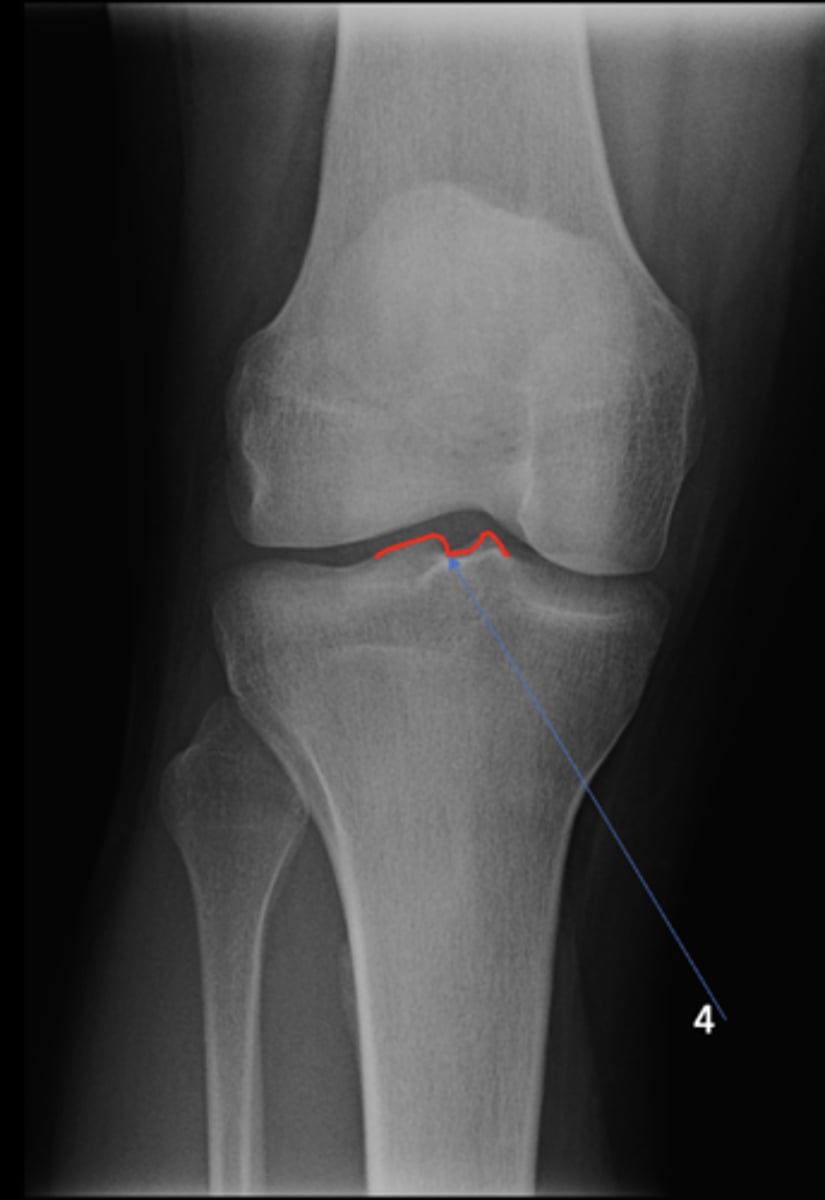

AP knee

View?

<p>View?</p>

49

New cards

Fibular head

ID 1

<p>ID 1</p>

50

Apex of fibular head

ID 2

<p>ID 2</p>

51

Fossa for popliteal tendon

ID 3

<p>ID 3</p>

52

Intercondylar eminence

ID 4

<p>ID 4</p>

53

Superior aspect of patella

ID 5

<p>ID 5</p>

54

Lateral femoral condyle

ID 6

<p>ID 6</p>

55

Medial femoral condyle

ID 7

<p>ID 7</p>

56

Intercondylar fossa

ID 8

<p>ID 8</p>

57

Apex of patella

ID 9

<p>ID 9</p>

58

Lateral femoral epicondyle

ID 10

<p>ID 10</p>

59

Medial femoral epicondyle

ID 11

<p>ID 11</p>

60

Tibial tuberosity

ID 12

<p>ID 12</p>

61

Medial tibial plateau

ID 13

<p>ID 13</p>

62

Lateral tibial plateau

ID 14

<p>ID 14</p>

63

Medial tibial condyle

ID 15

<p>ID 15</p>

64

Lateral tibial condyle

ID 16

<p>ID 16</p>

65

Physeal scar

ID 17

<p>ID 17</p>

66

Adductor tubercle

ID 18

<p>ID 18</p>

67